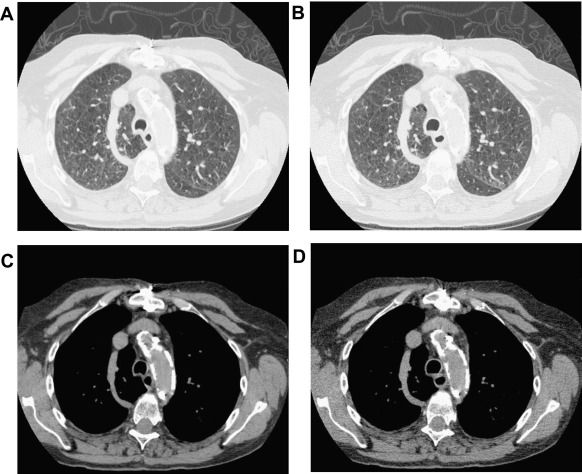

A multi-year agreement with a large Chile-based supplier of raw iodine is part of GE Healthcare’s commitment to increase the production of iodinated contrast media, commonly used in computed tomography imaging, by 30 million annually in 2025.